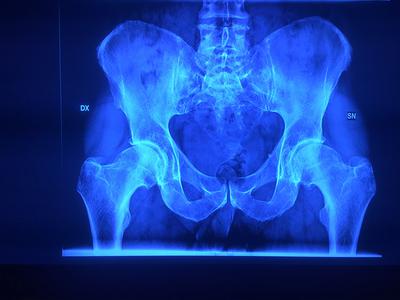

The doctor says I could be looking at an operation in 2 to 3 years (see images), which I found rather alarming.

You do indeed have early hip arthritis on both sides, and I doubt if any of the three alternatives appeal to you. But I can assure you, there is life after marathon running. It's just time to find another sport.